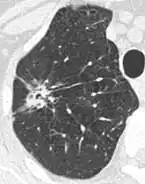

- Location: Upper lobe location is a risk factor for cancer, while a location close to a fissure or the pleura indicates a benign lymph node,[8] especially if having a triangular shape.[9]

- Margin morphology: a spiculated margin is a risk factor for cancer.[8] Benign causes tend to have a well defined border, whereas lobulated lesions or those with an irregular margin extending into the neighbouring tissue tend to be malignant.[10] In particular, spiculations are highly predictive of malignancy with a positive predictive value up to 90%.[9] Also, a "notch sign", which is an abrupt indentation of the nodule, increases the risk of cancer, but may also be found in granulomatous diseases.[9]

- Round well-delineated solid lung nodule with smooth border.[9]

- Lobulated nodule.[9]

- Spiculated lung nodule.[9]

- A "notch sign".[9]

- A triangular perifissural node can be diagnosed as a benign lymph node.[9]